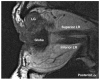

Methods: Five male and three female affected members of two autosomal dominant DURS2 pedigrees were enrolled in the study. Coronal T(1)-weighted MRI of the orbits was obtained in multiple gaze positions, as well as with heavy T(2) weighting in the plane of the cranial nerves. MRI findings were correlated with motility. V体育安卓版.

Results: All subjects had unilateral or bilateral limitation of abduction, or of both abduction and adduction, with palpebral fissure narrowing and globe retraction in adduction. Orbital motor nerves were typically small, with the abducens nerve (cranial nerve [CN]6) often nondetectable. Lateral rectus (LR) muscles were structurally abnormal in seven subjects, with structural and motility evidence of oculomotor nerve (CN3) innervation from vertical rectus EOMs leading to A or V patterns of strabismus in three cases V体育ios版. Four cases had superior oblique, two cases superior rectus, and one case levator EOM hypoplasia. Only the medial and inferior rectus and inferior oblique EOMs were spared. Two cases had small CN3s. .

Conclusions: DRS linked to the DURS2 locus is associated with bilateral abnormalities of many orbital motor nerves, and structural abnormalities of all EOMs except those innervated by the inferior division of CN3. The LR may be coinnervated by CN3 branches normally destined for any other rectus EOMs. Therefore, DURS2-linked DRS is a diffuse congenital cranial dysinnervation disorder involving but not limited to CN6. VSports最新版本.